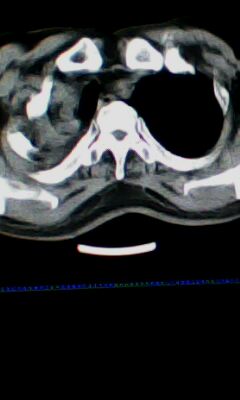

标题: CT25675:男 71 肺癌部分切除术后 3年 [打印本页]

标题: CT25675:男 71 肺癌部分切除术后 3年

右肺癌切除术后。

1.右肺符合肿瘤切除术后ct表现。